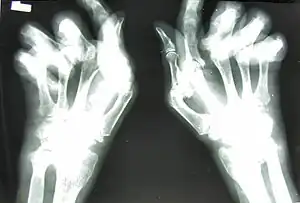

For a person with arthritis mutilans in the hands, the fingers become shortened by arthritis, and the shortening may become severe enough that the hand looks paw-like, with the first deformity occurring at the interphalangeal and metacarpophalangeal joints. The excess skin from the shortening of the phalanx bones becomes folded transversely, as if retracted into one another like opera glasses, hence the description la main en lorgnette. As the condition worsens, luxation, phalangeal and metacarpal bone absorption, and skeletal architecture loss in the fingers occurs.[5]

Enthesitis can assist in differentiating arthritis mutilans' parent condition psoriatic arthritis from rheumatoid arthritis and osteoarthritis, with evidence in plain radiographs (x-rays) and MRI as periostitis, new bone formation, and bone erosions.[7] Dactylitis, spondylitis and sacroiliitis are common with the parent condition psoriatic arthritis, but are not in rheumatoid arthritis.[9] MRI bone edema scores are high in arthritis mutilans and correlate with radiographic measures of joint damage, although they may not correlate with disease activity.[10] A source of significant pain, bone marrow edema (or lesions, using newer terminology), can be detected on MRI or with ultrasonography by signals of excessive water in bone marrow.[11] Specifically, bone marrow edema can be detected within bone on T1-weighted images as poorly defined areas of low signal, with a high signal on T2-weighted fat-suppressed images.[12] Comparatively, with arthritis mutilans in rheumatoid arthritis, bone marrow edema often involves the subchondral bone layer, while the condition as a subtype of psoriatic arthritis includes a greater extent of marrow edema, expanding to diaphysis.[10][13]